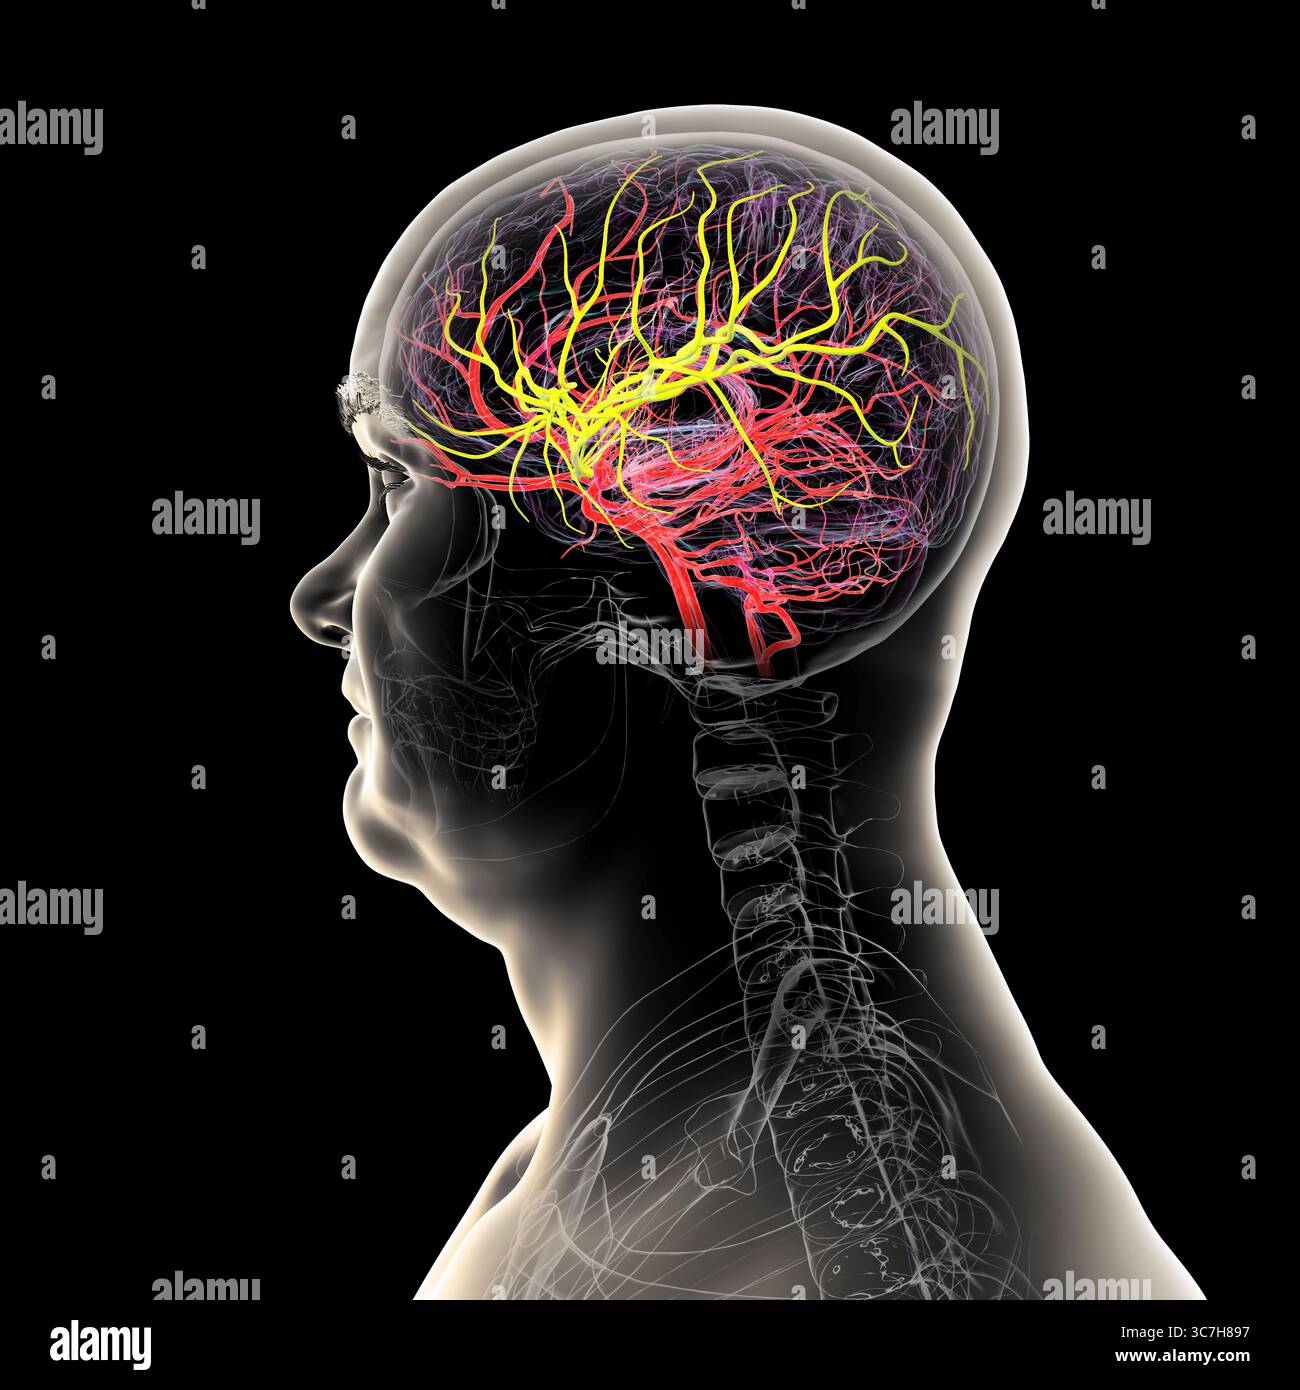

RF3C7H8AB–Darstellung der arteriellen Blutversorgung des Gehirns mit hervorgehobener Arteria cerebri Media (gelb), die Blut zu den frontalen, temporalen und parietalen Lappen liefert, entscheidend für die Gehirnfunktion.

RF3C7H897–Darstellung der arteriellen Blutversorgung des Gehirns mit hervorgehobener Arteria cerebri Media (gelb), die Blut zu den frontalen, temporalen und parietalen Lappen liefert, entscheidend für die Gehirnfunktion.

RF3C7H892–Darstellung der arteriellen Blutversorgung des Gehirns mit hervorgehobener Arteria cerebri Media (gelb), die Blut zu den frontalen, temporalen und parietalen Lappen liefert, entscheidend für die Gehirnfunktion.

RF3C7H890–Darstellung der arteriellen Blutversorgung des Gehirns mit hervorgehobener Arteria cerebri Media (gelb), die Blut zu den frontalen, temporalen und parietalen Lappen liefert, entscheidend für die Gehirnfunktion.